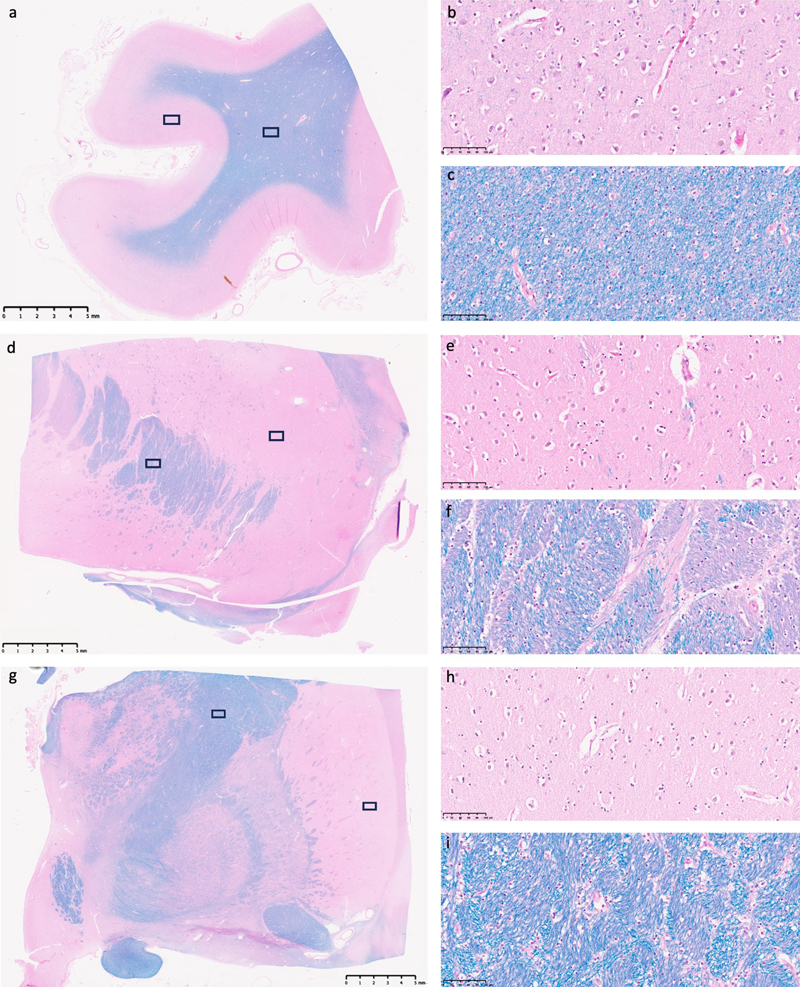

Qualitatively, we found that the overall tissue preservation visible on light microscopy across all examined samples maintained cellular structures that were generally discernible and identifiable (Figure 1). Expected postmortem artifacts were present, especially pericellular rarefactions, perivascular rarefactions, and vacuolization of the parenchyma. Otherwise, the cellular morphology appeared largely as expected across all regions, with neurons, glia, and blood vessels retaining their characteristic shapes. Luxol fast blue staining of myelin was also present across samples. We could not identify clear qualitative differences in the preservation quality between the surface areas (frontal cortex) and the inner areas (anterior and posterior striatum) of the hemi-sectioned brain specimens, although there were inherent differences in cellular morphology between regions that prevented us from performing quantitative comparisons of cell shape or other cellular features as a proxy for preservation quality. In a few cells across all three brain regions, we detected what potential signs of early necrosis, such as partially disrupted membranes, but these were not widespread or common enough to distinguish them from potential artifacts, such as staining inconsistencies or image blurring.

Figure 1. Representative light microscopy images from several brain region studied. LHE-stained tissue sections from the frontal cortex (a–c), anterior striatum (d–f), and posterior striatum (g–i) of an immersion-fixed hemi-sectioned brain specimen. Panel (a) shows a low-magnification overview of the frontal cortex, with black rectangles indicating regions of interest examined at higher magnification in (b) of gray matter and in (c) of white matter. Similar triads of representative images are shown for the anterior striatum (d–f) and the posterior striatum (g–i). All samples were obtained from a 63-year-old male brain donor who died of respiratory failure due to malignant mesothelioma, with a PMI of 23.6 h before tissue preservation. Scale bars in (a, d, and g) are 5 mm; scale bars in higher magnification images are 100 μm.